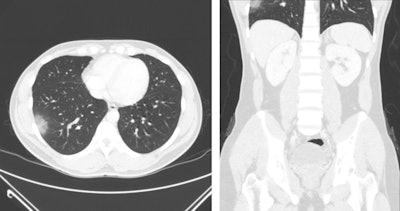

Of the 119 patients, 101 had abdomen/pelvis CT and 18 had cervical spine/neck CT. The researchers found the following:

- The most common CT lung findings were ground-glass opacity (96%) and consolidation (40%).